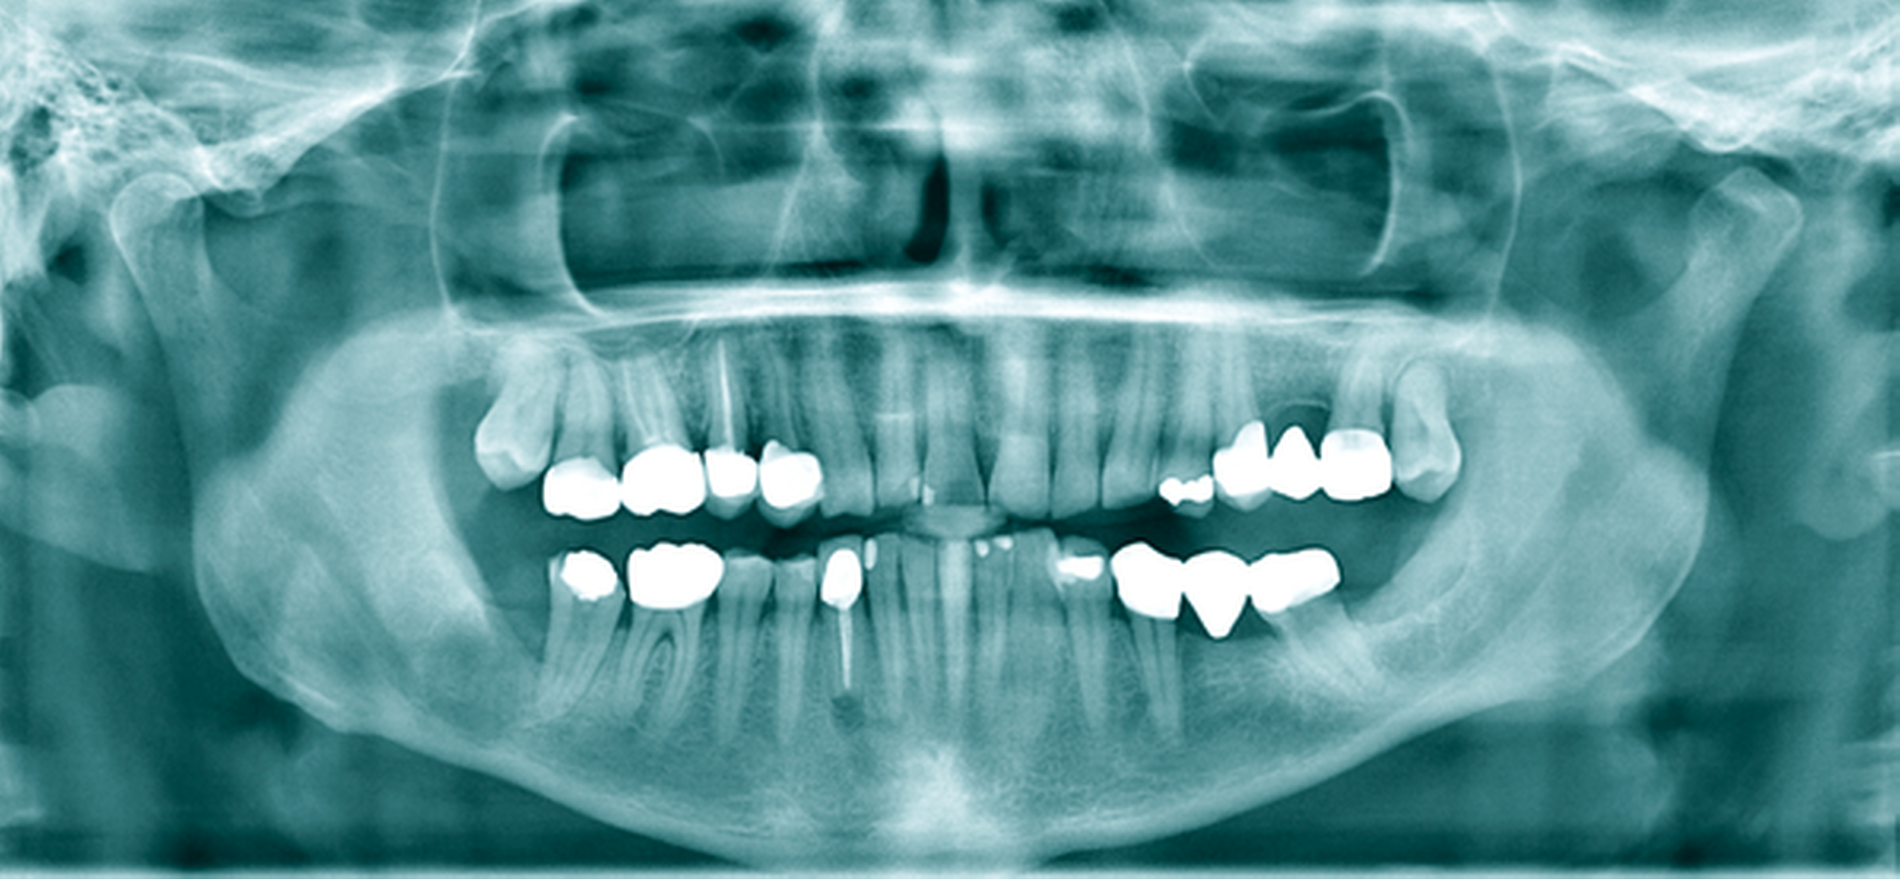

Eine 72-jährige Patientin wurde zur Therapie einer Zyste in regio 48 in unser MVZ überwiesen. Es handelte sich um einen Zufallsbefund im OPTG. Klinische Beschwerden wurden von der Patientin verneint (Abbildung 2a). Vorerkrankungen bestanden abgesehen von Migräne nicht. Zur Beurteilung der Zystenausdehnung erfolgte eine Computertomografie des Gesichtsschädels, die insbesondere eine basal stark ausgedünnte Kortikalis zeigte. Nach Erörterung der therapeutischen Möglichkeiten entschied sich die Patientin für eine Zystostomie, da die Zystektomie mit einem erheblichen Frakturrisiko, der möglichen Schädigung des N. alveolaris inferior sowie einer Behandlung in Allgemeinanästhesie verbunden gewesen wäre. In Lokalanästhesie wurde über einen marginalen Zugang in regio 47-48 eine Biopsie des Zystenbalgs gewonnen sowie eine Drainage ins Zystenlumen inseriert. Histologisch konnte eine follikuläre Zyste gesichert werden.

Die täglichen Spülungen des Lumens über die einliegende Drainage mit NaCl-Lösung erfolgten durch die Patientin selbst nach entsprechender Instruktion. Dies führte sie für sechs Monate selbstständig durch. Zwischenzeitlich musste das Drainageröhrchen wegen Verlusts erneut inseriert werden. Im DVT zeigte sich nach sechs Monaten eine signifikante Ossifikation am Rande des Zystenlumens und der N. alveolaris inferior wies wieder eine knöcherne Ummantelung auf (Abbildung 2b). Somit konnten die Zystektomie des verbliebenen Befunds und die Entfernung von 48 in ITN erfolgen. Dabei und postoperativ traten keine Komplikationen auf. Zahn 47 ist unverändert vital. Die extrem verlagerten Zähne 18 und 28 wurden auf Wunsch der Patientin belassen. Nach vier Monaten stellt sich im OPTG ein nahezu vollständig ossifizierter Defekt dar und die Patientin ist vollkommen beschwerdefrei (Abbildung 2c).